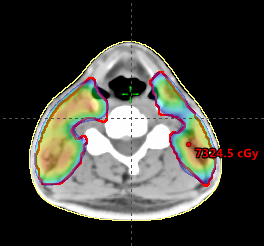

Fazal Khan

Score: 99.1/ 100

Hospital: Mayo Clinic – Arizona

Technique: IMPT

Rank: Top RayStation

Job Title: Medical Dosimetrist